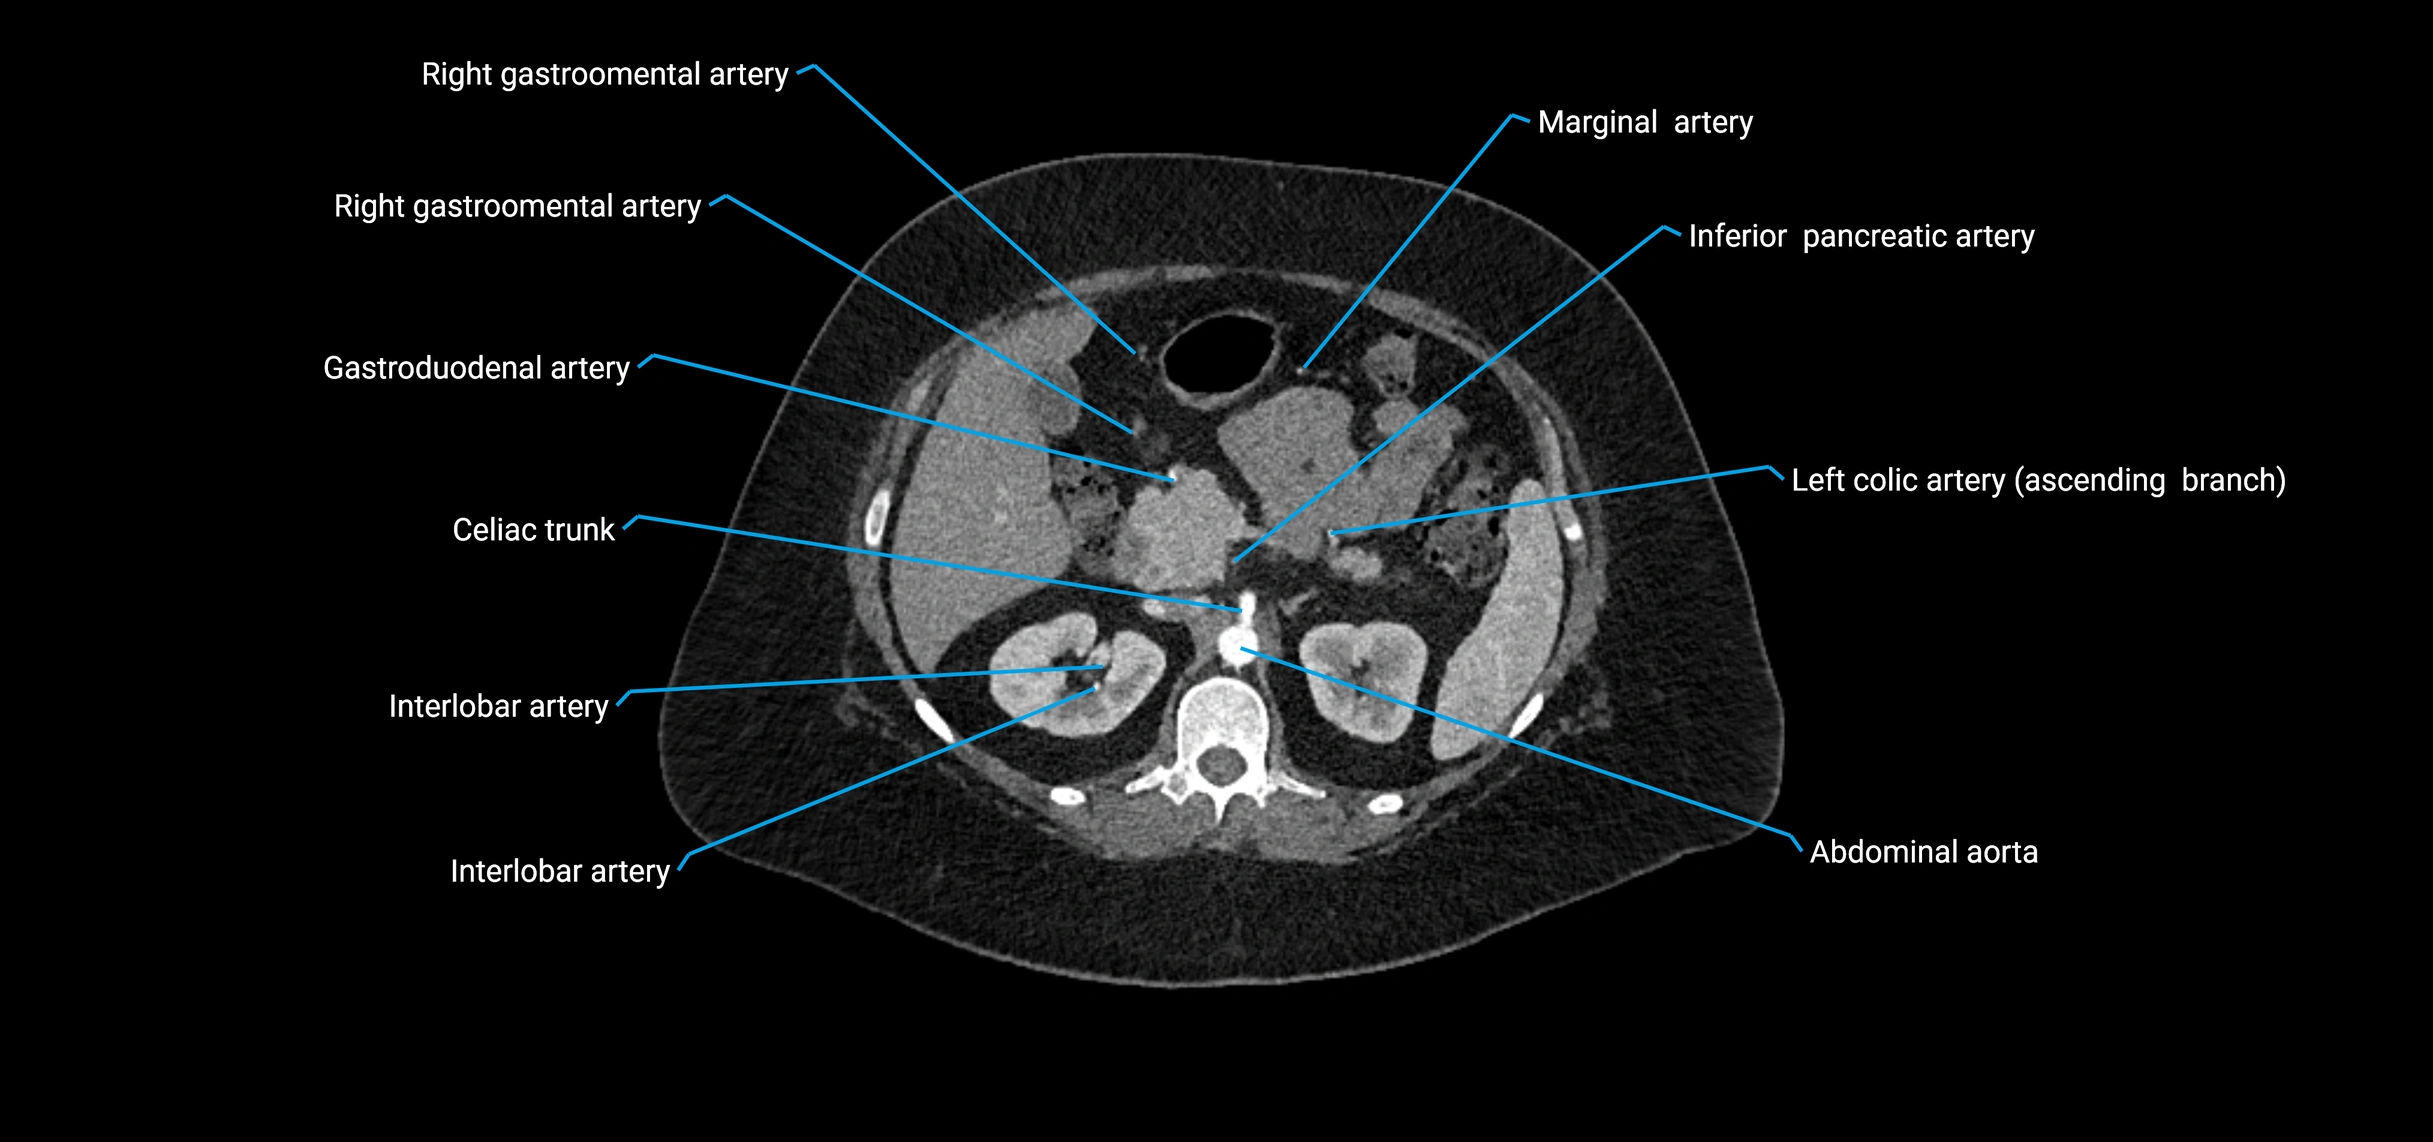

The abdominal aorta is the continuation of the thoracic aorta, beginning at the level of the aortic hiatus of the diaphragm (T12 vertebra) and terminating at the level of the L4 vertebra where it bifurcates into the right and left common iliac arteries. It lies slightly to the left of the midline and courses anterior to the vertebral bodies, surrounded by the retroperitoneal structures of the abdomen.

The abdominal aorta gives off numerous visceral and parietal branches, supplying the abdominal organs, pelvic structures, and lower limbs. It is the main conduit of oxygenated blood from the heart to the abdomen and lower body. The aorta is clinically significant as the common site of aneurysm, dissection, atherosclerosis, and traumatic injury.

Branches

• Unpaired visceral branches: celiac trunk, superior mesenteric artery (SMA), inferior mesenteric artery (IMA)

• Paired visceral branches: middle suprarenal arteries, renal arteries, gonadal arteries (testicular or ovarian)

Contrast-enhanced CT (CTA):

• Gold standard for abdominal aortic imaging

• Provides excellent detail of lumen, wall, aneurysm, thrombus, and branch vessels

• Multiplanar and 3D reconstructions help in aneurysm measurement, stent graft planning, and dissection evaluation

• Detects acute rupture, traumatic injury, or occlusion with high sensitivity